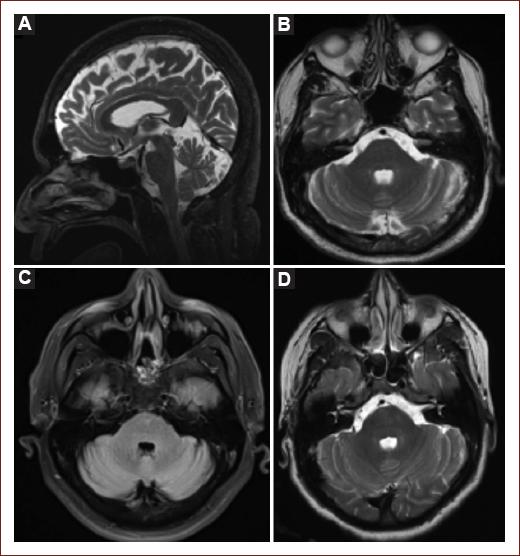

MRI was available in three patients, neither of whom presented any brainstem abnormalities (Fig. 1). One patient underwent 18F-FDG PET-CT, showing generalized cortical hypometabolism; hypermetabolism was visualized in the striatum (St) bilaterally (Fig. 2).

Figure 1 Normal brain MRI in subjects with BBE. A: sagittal T2; B: axial T2 from patient 1; C: axial T2 FLAIR from patient 2; D: axial T2 from patient 4.

GBS has been classically described as a post-infectious autoimmune entity with exclusive affection to the peripheral nerves; however, BBE also involves CNS structures14. The mechanism by which the GQ1b antibodies cause clinical manifestations is because GQ1b is highly expressed in muscle spindles, important proprioceptive transducers within the muscles, and when binded to the anti GQ1b antibodies they produce the characteristic combination of symptoms2,14. The same is not the case with BBE, where little is known about the pathophysiological mechanism in which the ascending reticular activating system of the brainstem is involved. It has been hypothesized that there may be GQ1b among the brainstem structures; but this has not been proven2. One histopathologic postmortem study reported perivascular inflammation on the brainstem6, and another study demonstrated changes on the BBB permeability in the area postrema that may allow some molecules, such as antibodies, to penetrate the CNS15. Other studies have shown brainstem involvement in BBE with MRI with findings that correspond to changes of intensity in 11% of cases12. In our population, none of the patients had abnormalities on the MRI.